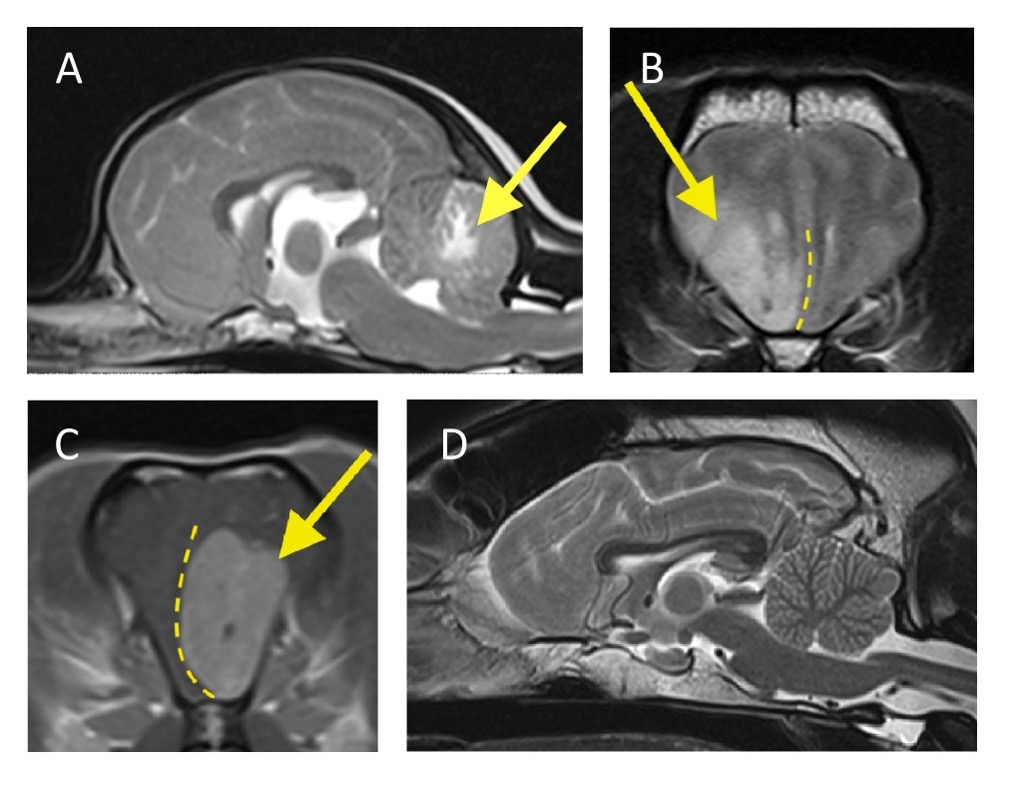

Figur 1. Eksempler på MR-fund. A) T2-vægtet længdesnit. Rostralt er til venstre i billedet. I cerebellum ses en hyperintens intra-axial læsion (pil), primært i den hvide substans. Patienten havde to lignende læsioner i cerebrum (ikke vist her). Den primære MR-diagnose var meningoencephalitis af ukendt oprindelse (MUO). Diagnosen blev bekræftet ved post mortem histopatologi. B) T2-vægtet tværsnit. Patientens højre side er til venstre i billedet. I højre frontallobe ses en hyperintens intra-axial læsion (pil). Læsionen har en diffus kontur og involverer især den grå substans. Den displacerer højre frontallobe over midtlinjen (stiplet linje). Den primære MR-diagnose var neoplasi, f.eks. gliom, hvilket blev bekræftet ved post-mortem histopatologi. C) T1-vægtet tværsnit, post-kontrast. Patientens højre er til venstre i billedet. I området ved venstre frontallobe ses en veldefineret, oval, extra-axial læsion (pil). Læsionen er hyperintens pga. kontrastforstærkning og displacerer midtlinjen mod højre (stiplet linje). Den primære MR-diagnose var meningiom. D) T2-vægtet længdesnit. Upåfaldende MR-scanning.

Meningoencephalitis af ukendt oprindelse var den hyppigste diagnose blandt hunde med intra-axiale MR forandringer. MUO rammer typisk voksne hunde af små racer. Sygdommen er progressiv og dødelig, hvis den ikke behandles (4). Ved MUO ses oftest multifokale læsioner på MR, men de kan også være fokale, hvilket kan gøre dem svære at skelne fra fx intra-axial neoplasi (figur 1) (5). Intra-axial neoplasi udgjorde den næststørste undergruppe af intra-axiale forandringer. Multifokale forandringer på MR ses også ved andre sygdomsprocesser end blot MUO som hos de 2 hunde, der havde MUO som primær MR-diagnose, men på post-mortem histopatologisk undersøgelse fik konkluderet henholdsvis et infarkt og neoplasi.